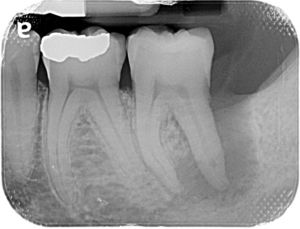

La pathologie pulpaire et les maladies parodontale partagent un organe cible commun : les tissus de soutien de la dent. Si leurs caractéristiques, leur diagnostic et leurs thérapeutiques propres sont habituellement aisés, la confluence sur une même racine d’une lésion parodontale et d’une lésion d’origine endodontique, aboutissant à une lésion endo-parodontale, complique largement autant le diagnostic que la thérapeutique.

La guérison de ces lésions combinées, relève de l’établissement d’un diagnostic précis et d’une thérapeutique adaptée.

Cette présentation a pour objectif de faire l’état des lieux des connaissances utiles à l’appréhension des lésions endo-parodontales (voies de communication, classifications) et d’illustrer les démarches diagnostiques et thérapeutiques à travers plusieurs cas cliniques.